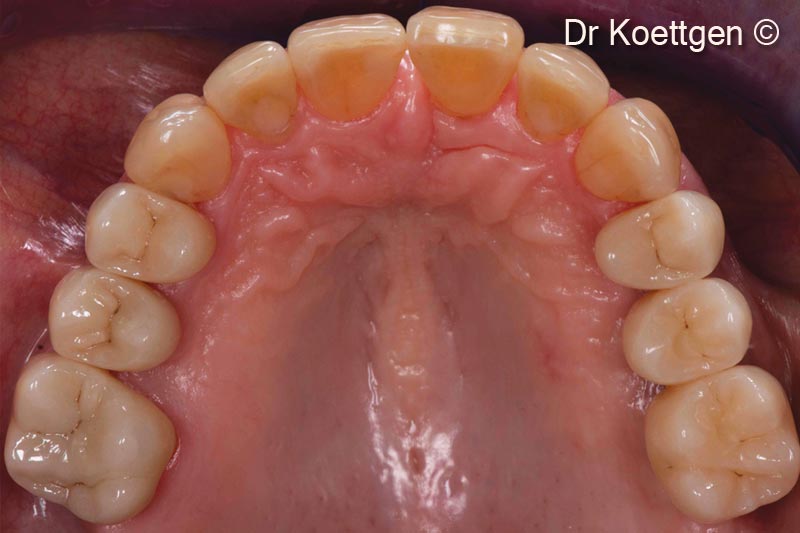

15. Final situation